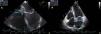

A 57-year-old man was referred to the hospital for evaluation of a right hilar lung mass discovered on a chest X-ray performed because of a persistent cough, increasing effort dyspnea and deterioration of the general condition. He has no medical history and had smoked 35 packs a year. On the admission, physical examination showed a slow heart rate at 40 beats per minute. The electrocardiogram showed a complete atrioventricular block. On echocardiography, a 26×17mm mass was noted in the basal area of the atrial septum without interfering with the mitral valve function (Fig. 1). A thoracic computed tomography (CT) scan revealed a right pulmonary hilum mass with mediastinal and peritoneal lymphadenopathy, adrenal metastasis, and a low-density mass located on the interatrial septum (Fig. 2). Fiberoptic bronchoscopy showed stenosis with mucosal tumor infiltration in the right upper lobe bronchus. The bronchial biopsy revealed a moderately differentiated adenocarcinoma. Based on these findings, the atrioventricular block was associated with interatrial septum metastasis of the lung adenocarcinoma. A pacemaker was implanted and pemetrexed platinum chemotherapy was started.